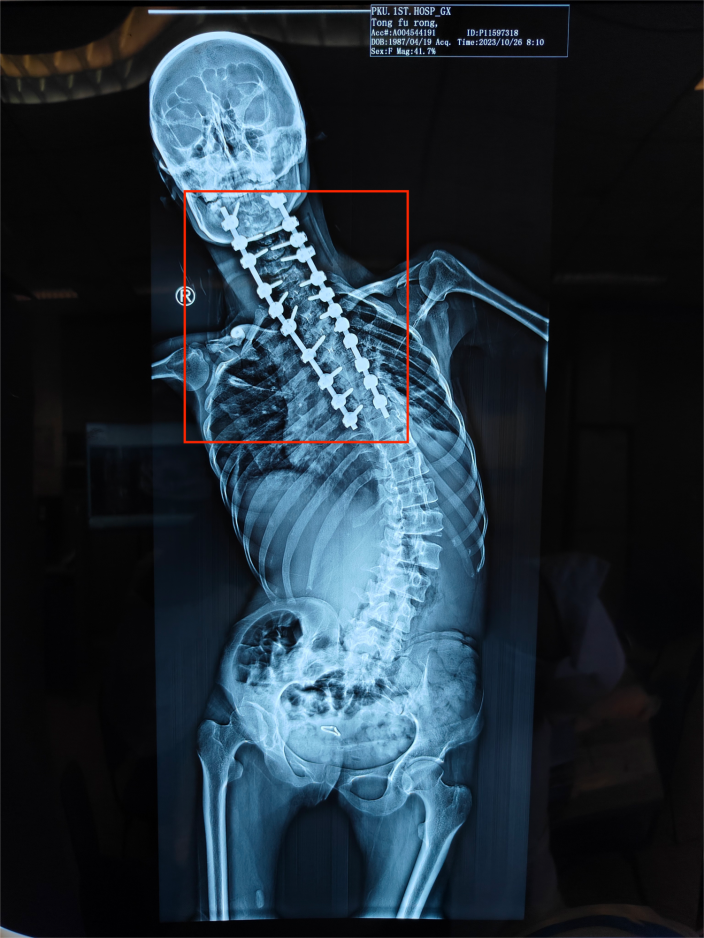

這是一場“天花板級別”的手術。童福容的背部被整個打開,暴露出神經密佈的脊柱,22顆螺釘被依次植入側彎的椎體裏,加上4根筷子粗的鈦棒,她反向摺疊180度的身體就這樣被拉直了。

童福容第一次手術後,紅色部分為固定脊柱的螺釘

受訪者供圖

中午十二點左右,王宇走進手術室,進行手術最關鍵的部分。他藉助導航系統將22顆椎弓根螺釘依次植入到患者脊柱並進行固定,然後再進行植骨融合和縫合操作。手術室裏不斷髮出釘子與骨頭碰撞後的清脆聲音。